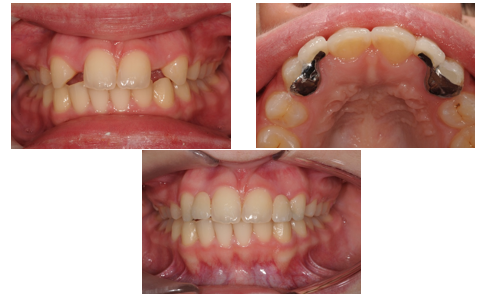

What are resin-retained cantilever bridges?

Bridges where the pontic is retained by a metal retainer using cement and abutment coverage.

cantilver= one side only attachment

What is the clinical workflow for resin-retained bridges?

Primary impression. Diagnostic wax-up. Master impression. Bridge construction. Bridge trial and cementation.

What are design considerations for resin-retained bridges?

Light contact for the pontic in ICP. Discuss anterior wax-up with patients. Inform patients that metal wings may show through.